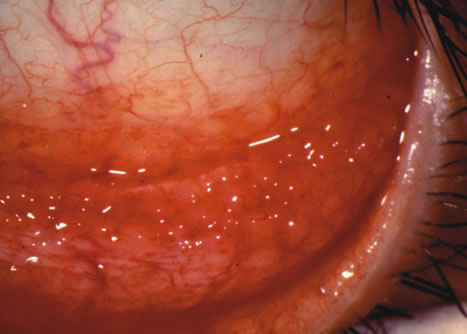

Clinically, follicles are yellowish to grayish white, discrete, round elevations of the conjunctiva. The central part of the follicle is avascular, but dilated blood vessels may surround the base and sweep up from the base over the convexity (Figs. 1 and 2). Follicles are 0.2 to 2 mm in size, although larger follicles may be seen, particularly in chlamydial disease.3

Fig. 1. Nonspecific follicular conjunctivitis demonstrating the classical appearance of follicles in the inferior fornix. (Courtesy of Peter R. Laibson, MD.)

Fig. 2. Follicular conjunctival reaction in the inferior fornix.